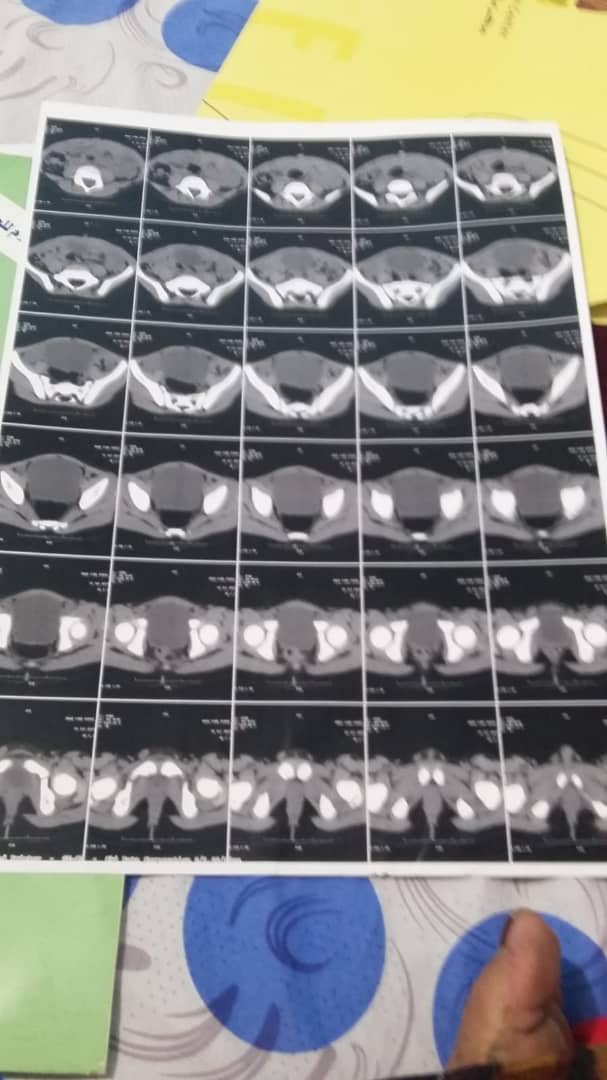

وقال المواطن "فهد عثمان" في مناشدة بعث بها لوسائل الإعلام ان طفله (عمر) البالغ من العمر ست سنوات يعاني من ورم في الكلى وانسداد في مجرى البول, مما قد يسبب له ذلك فشل كلوي.

وأوضح المواطن في مناشدته الإنسانية أن طفله لم يعد يتحمل الآلم وعبر أصحاب الخير سافر به إلى جمهورية مصر لإجراء الفحوصات, حيث طلب منه الأطباء إجراء عملية جراحية عاجلة لإستصال الورم وفتح انسداد مجرى البول.